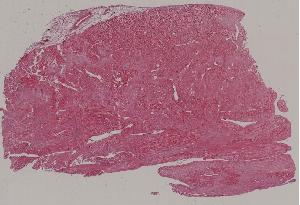

47.心肌梗死